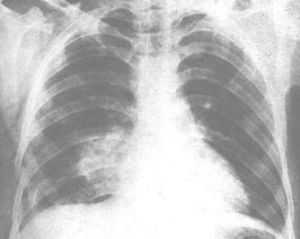

由於肺挫傷的嚴重程度和範圍大小不同,臨床表現有很大的差異。輕者僅有胸痛、胸悶、氣促、咳嗽和血痰等,聽診有散在羅音。X線胸片上有斑片狀陰影(常報告為創傷性濕肺)、1~2天即可完全吸收。血氣可正常。有人稱之為肺震盪。嚴重者則有明顯呼吸困難、發紺、血性泡沫痰、心動過速和血壓下降等。聽診有廣泛羅音、呼吸音減弱至消失或管型呼吸音。動脈血氣分析有低血氧症在胸片尚未能顯示之前具有參考價值。X線胸片是診斷肺挫傷的重要手段。其改變約70%病例在傷後1小時內出現,30%病例可延遲到傷後4~6小時,範圍可由小的局限區域到一側或雙側,程度可由斑點狀浸潤、瀰漫性或局部斑點融合浸潤、以致瀰漫性單肺或雙肺大片浸潤或實變陰影。經治療後一般在傷後2~3天開始吸收,完全吸收需2~3周以上。近年來通過系列CT檢查,對肺挫傷提出新的病理觀點,X線平片上所顯示的挫傷表現在CT片上是肺實質裂傷和圍繞裂傷周圍的一片肺泡積血而無肺間質損傷。